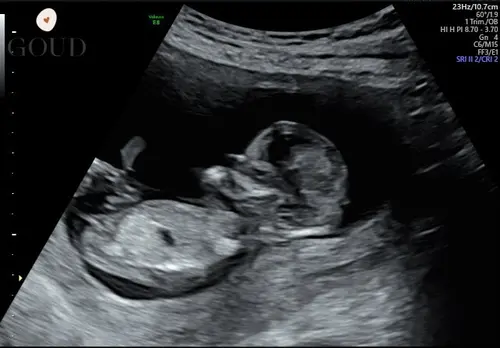

Ben benieuwd wat jullie denken dit is 12+4